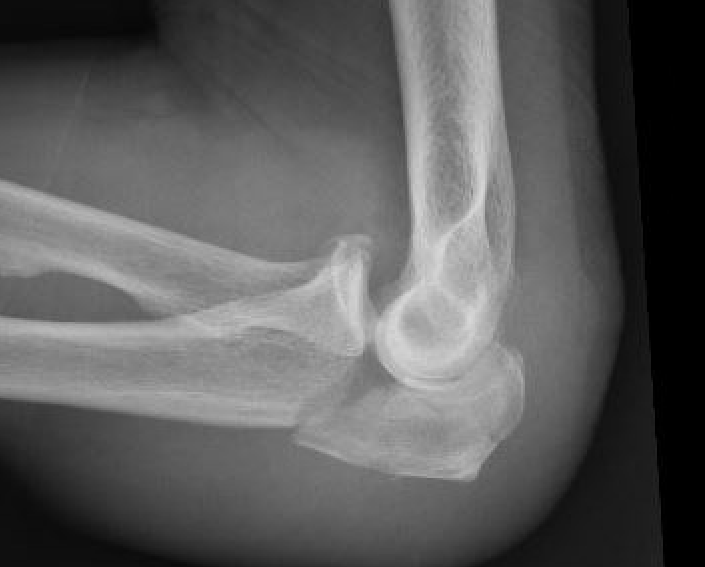

Monteggia variant

Definition

Elbow dislocation + olecranon fracture + radial head/neck fracture +/- coronoid fracture

Complex proximal ulna fracture with radial head replacement subluxation